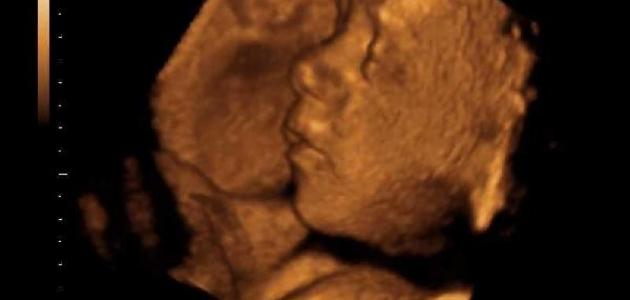

31 Неделя Фото Малыша

31 Неделя Фото Малыша 88 фото